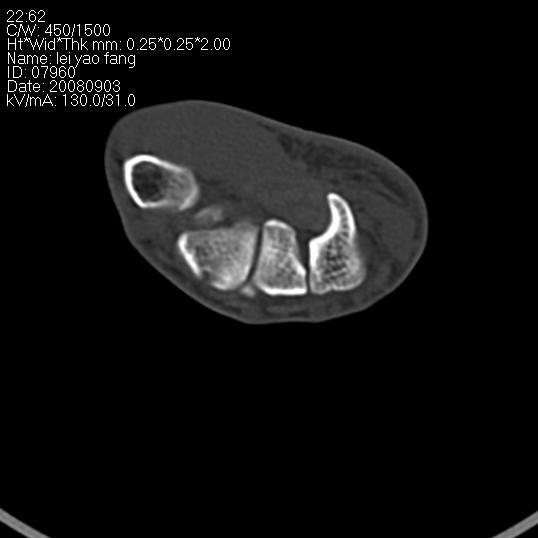

以下是引用杀毒软件在2008-9-4 17:41:00的发言:[br]考虑----舟骨囊肿